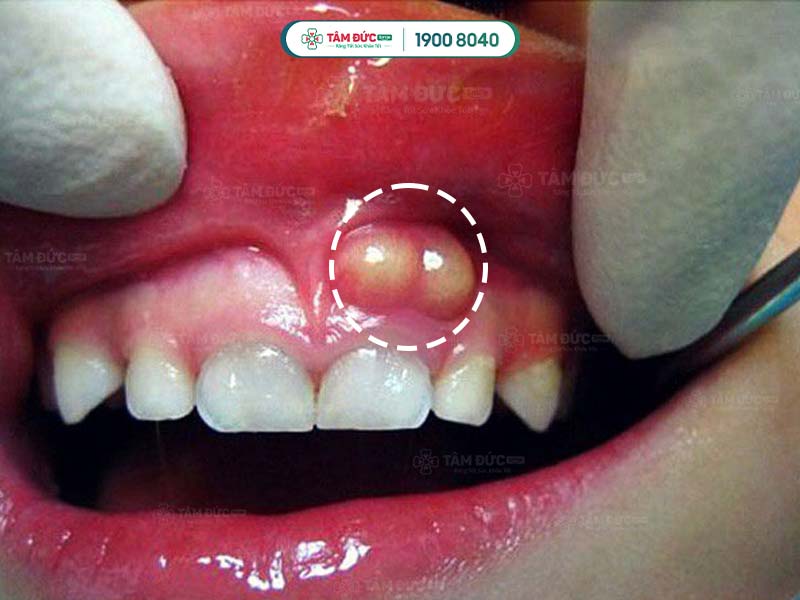

Sưng nướu răng hàm trên có mủ là trường hợp nướu răng hàm trên bị viêm nhiễm, sưng tấy và xuất hiện mủ.

Triệu chứng của sưng nướu bao gồm:

- Nướu răng sưng đỏ, đau nhức.

- Xuất hiện mủ ở nướu răng, chảy ra khi ấn vào.

Nướu răng hàm trên bị sưng và tụ mủ